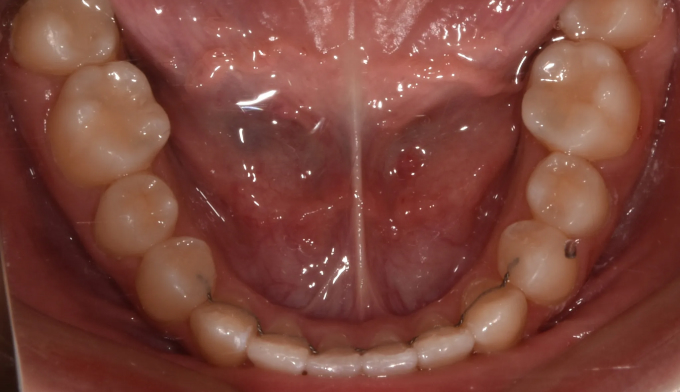

덧니뿐만 아니라 앞니의 교합이 좋지 않아 윗니가 아랫니를 덮지 못하는 개방교합도 동시에 나타납니다.

얇은 입술과 뒤로 들어간 입술을 가지고 있기 때문에 발치를 하지 않고 확장과 후방이동을 통해 최대한 공간을 마련하여 교정하기로 하였습니다.

총 교정기간은 21개월입니다.